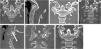

ResultsA total of 11 patients (8 men, 3 women; mean age 41.5 ± 18.2 years) underwent fully percutaneous transarticular C1-C2 fixation. The mean operative time was 115.0 ± 30.8 min for patients stabilized using a Halo device and 80.6 ± 33.2 min for those immobilized with a Mayfield clamp. The mean blood loss across all cases was 38.8 ± 8.7 mL. One patient died from concurrent cardiac pathology. Two patients were lost to follow-up due to relocation, leaving 8 patients for final assessment. At final follow-up, the mean VAS score was 2 ± 1.5 and the mean NDI score was 5.3 ± 5.2. All patients with preoperative neurological deficits improved by one level on the ASIA scale. Fusion was achieved in 7 of 8 cases (87.5%), and 1 patient (12.5%) developed a stable C1-C2 pseudoarthrosis.

ConclusionOur initial clinical experience demonstrated that fully percutaneous posterior transarticular C1-C2 stand-alone screw fixation using cannulated instruments could be a feasible and safe procedure. Critical requirements for this technique include complete reduction of atlantoaxial dislocation, compression in the lateral joint region, adequate intraoperative visualization, and strict adherence to specific screw trajectories.